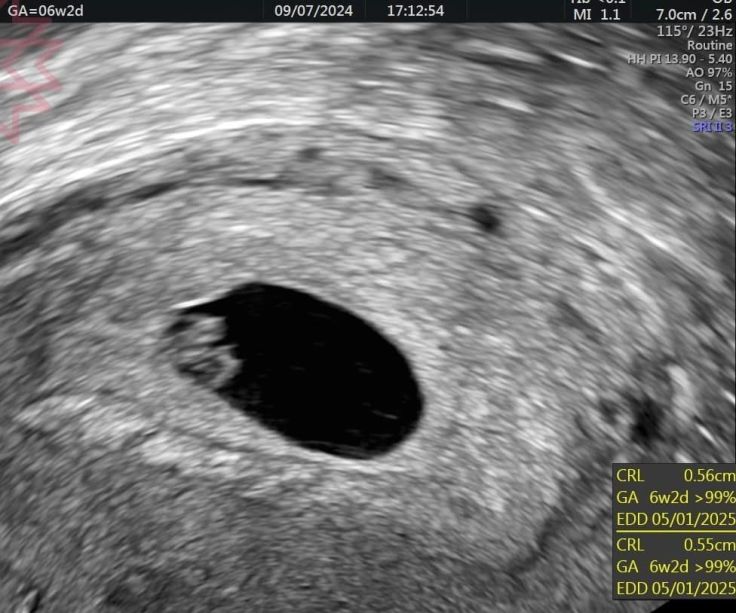

這是同一個媽咪同一天的超音波

超音波的第二張是從陰道超音波看到的

裡面卵黃囊跟胚胎非常清楚

我相信即便你沒有任何醫學背景只要有眼睛的也可以分辨到底哪一張比較清楚